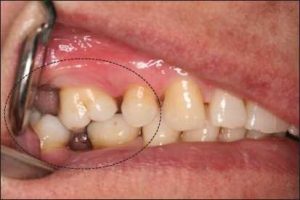

The loss of a single tooth or a group of teeth may lead to malposition of the remaining teeth due to their extrusion or tipping (Figure 10-4).

In most cases, the alveolar bone moves occlusally along with the extruded tooth (Figure 10-5). Although not always a practical solution, orthodontic treatment may be beneficial in managing occlusal discrepancies. Another treatment option is the surgical correction of the position of the tooth and the supporting alveolar bone.